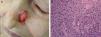

Cell differentiation (Figs. 2 and 3): well differentiated, moderately differentiated, or poorly differentiated

- -